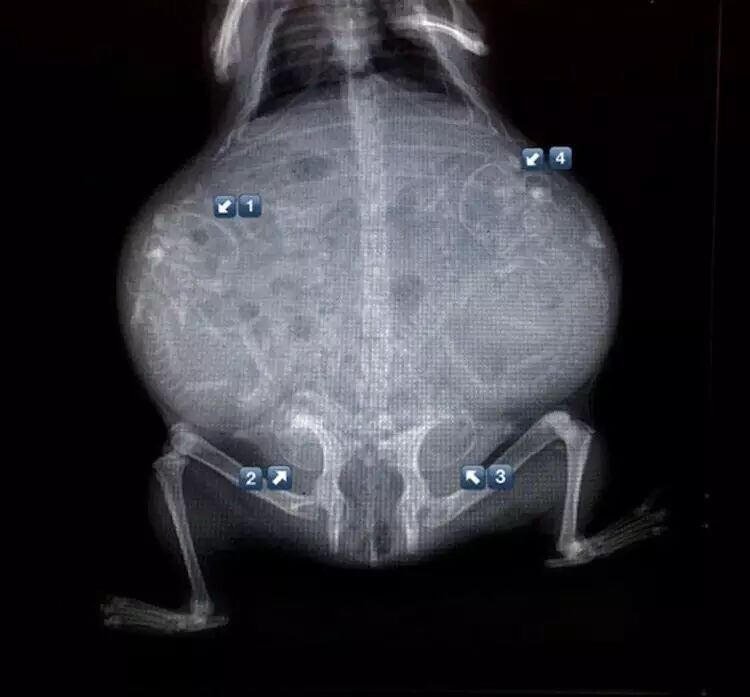

怀孕的天竺鼠。